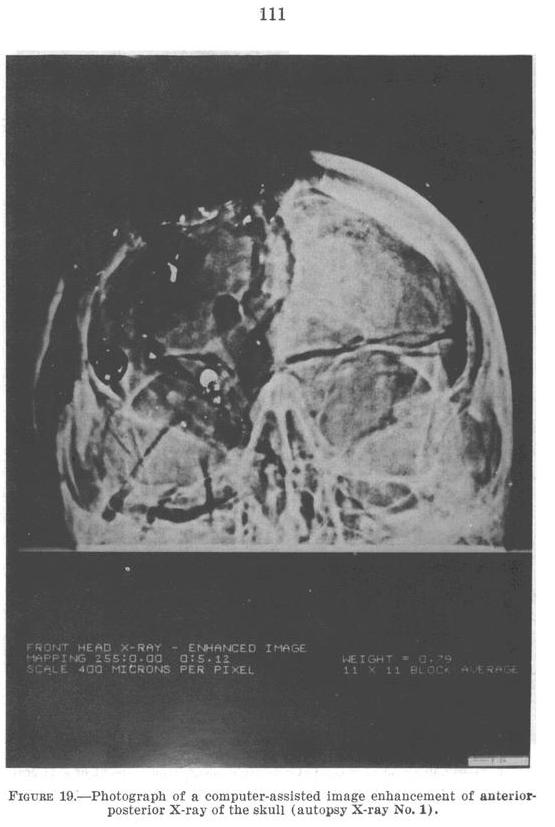

HSCA Appendix Volume 7

Figure 19, Page 111

Oswald Theorists claim that there is damage to the top-front

of the skull where the alleged rear bullet exited, but

claim that no bullet entered or exited the temple. Contrarily,

compare the left intact temple to the right damaged

temple

in HSCA Figure 19. Also notice the missing

temple bone in HSCA Figure 20. (click X-Rays to enlarge)